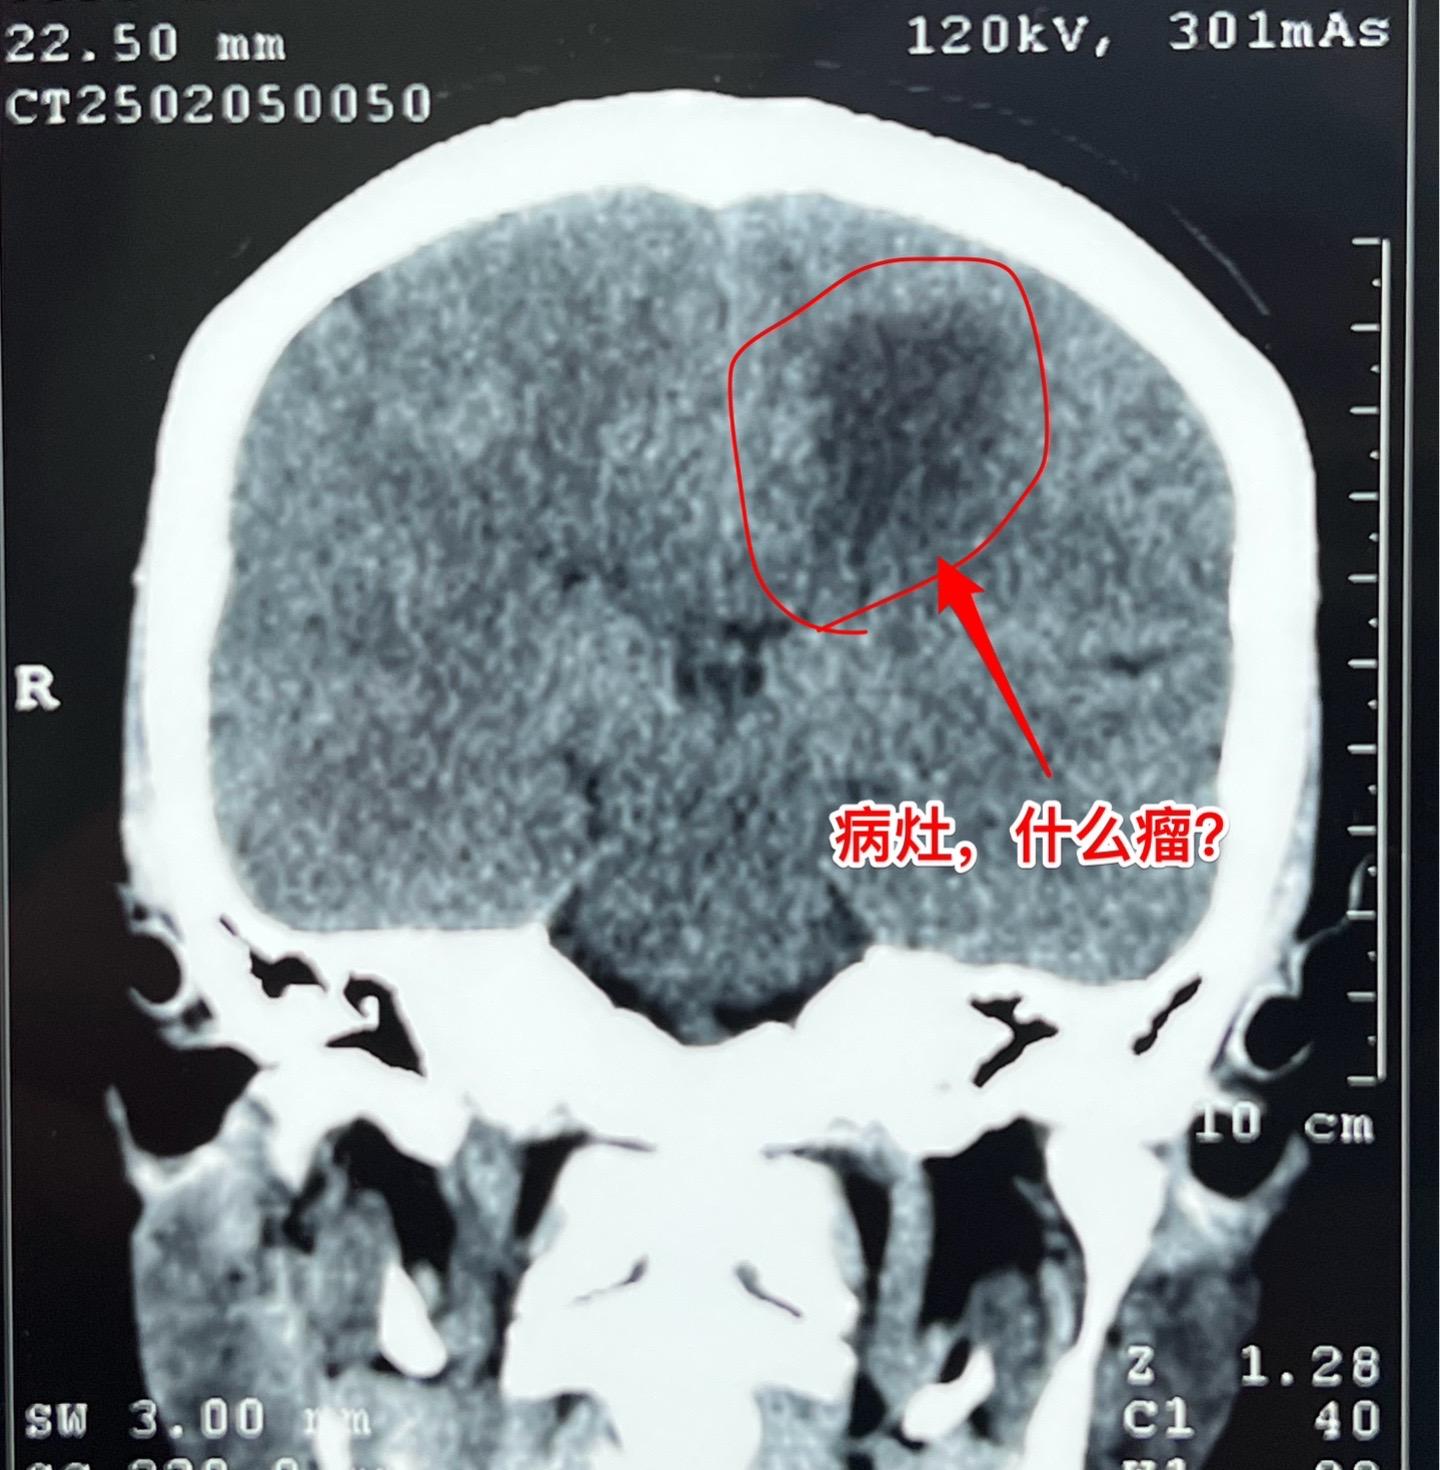

疾病多种多样,鉴别诊断不易!近几年人工智能AI发展迅猛,成果惊人! 听说有AI医院! 医生和病人都会提问:AI能取代医生看病吗? 今天介绍一个病人,61岁女性,因右侧偏身麻木无力来看病。CT和磁共振显示左侧中央区有个病灶,见图。怀疑是胶质瘤? 病人的症状越来越严重,正月初九住院后行走困难,而且右手手指难以张开,术前和病人家属充分交流、沟通,这个位置属于中央区,手术后很可能症状会加重。患者的两个儿子均想积极治疗。住院后两天做了手术。手术过程中发现